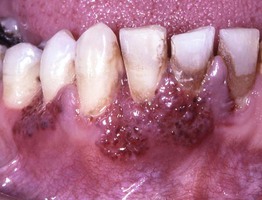

• Systemic diseases that can present with oral findings are listed in Table 59.1 (Figs. 59.15 and 59.16).

Fig. 59.16 Wegener's granulomatosis – strawberry gums. The affected areas of the gingiva are red-purple, micropapular, and friable, with a resemblance to ripe strawberries. Courtesy, Carl M. Allen, MD, and Charles Camisa, MD.